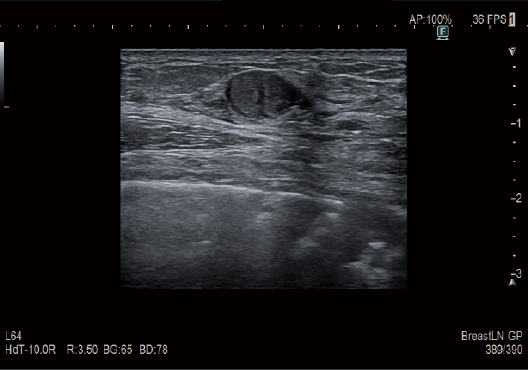

Gerçek Zamanlı Doku Elastografisi (RTE)

RTE, doku gerinimini gerçek zamanlı olarak değerlendirir ve doku sertliğini renk haritası olarak görüntüler. Uygulama, meme de dahil olmak üzere çok çeşitli klinik alanlarda doğrulanmıştır ve karaciğer fibroz evrelemesinin tahmini elastisite değerini hesaplamak mümkündür.